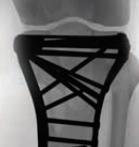

Proximal Tibia Fracture System

• The Proximal Tibia Fracture System is a comprehensive plating set designed for treatment of a variety of tibial plateau fractures.

• The system features three styles of Lateral Proximal Tibia Plates, a Medial Locking Plate, and a Posteromedial Buttress Plate to address intra-articular and extra-articular fractures of the proximal tibia.